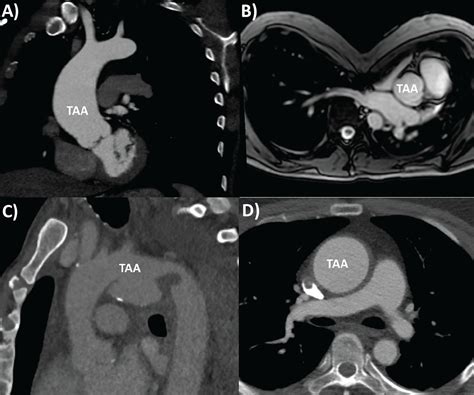

The Taa Medical Abbreviation stands for Temporal Arteritis. Temporal arteritis, also known as giant cell arteritis, is a type of vasculitis that affects the medium and large arteries, particularly the temporal arteries located on the sides of the head. This condition is characterized by inflammation of the arteries, which can lead to a variety of symptoms and complications if left untreated.